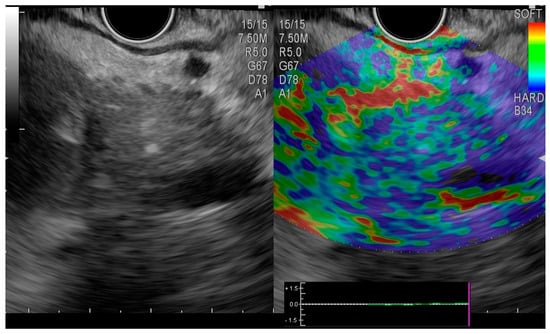

2. Case Presentation